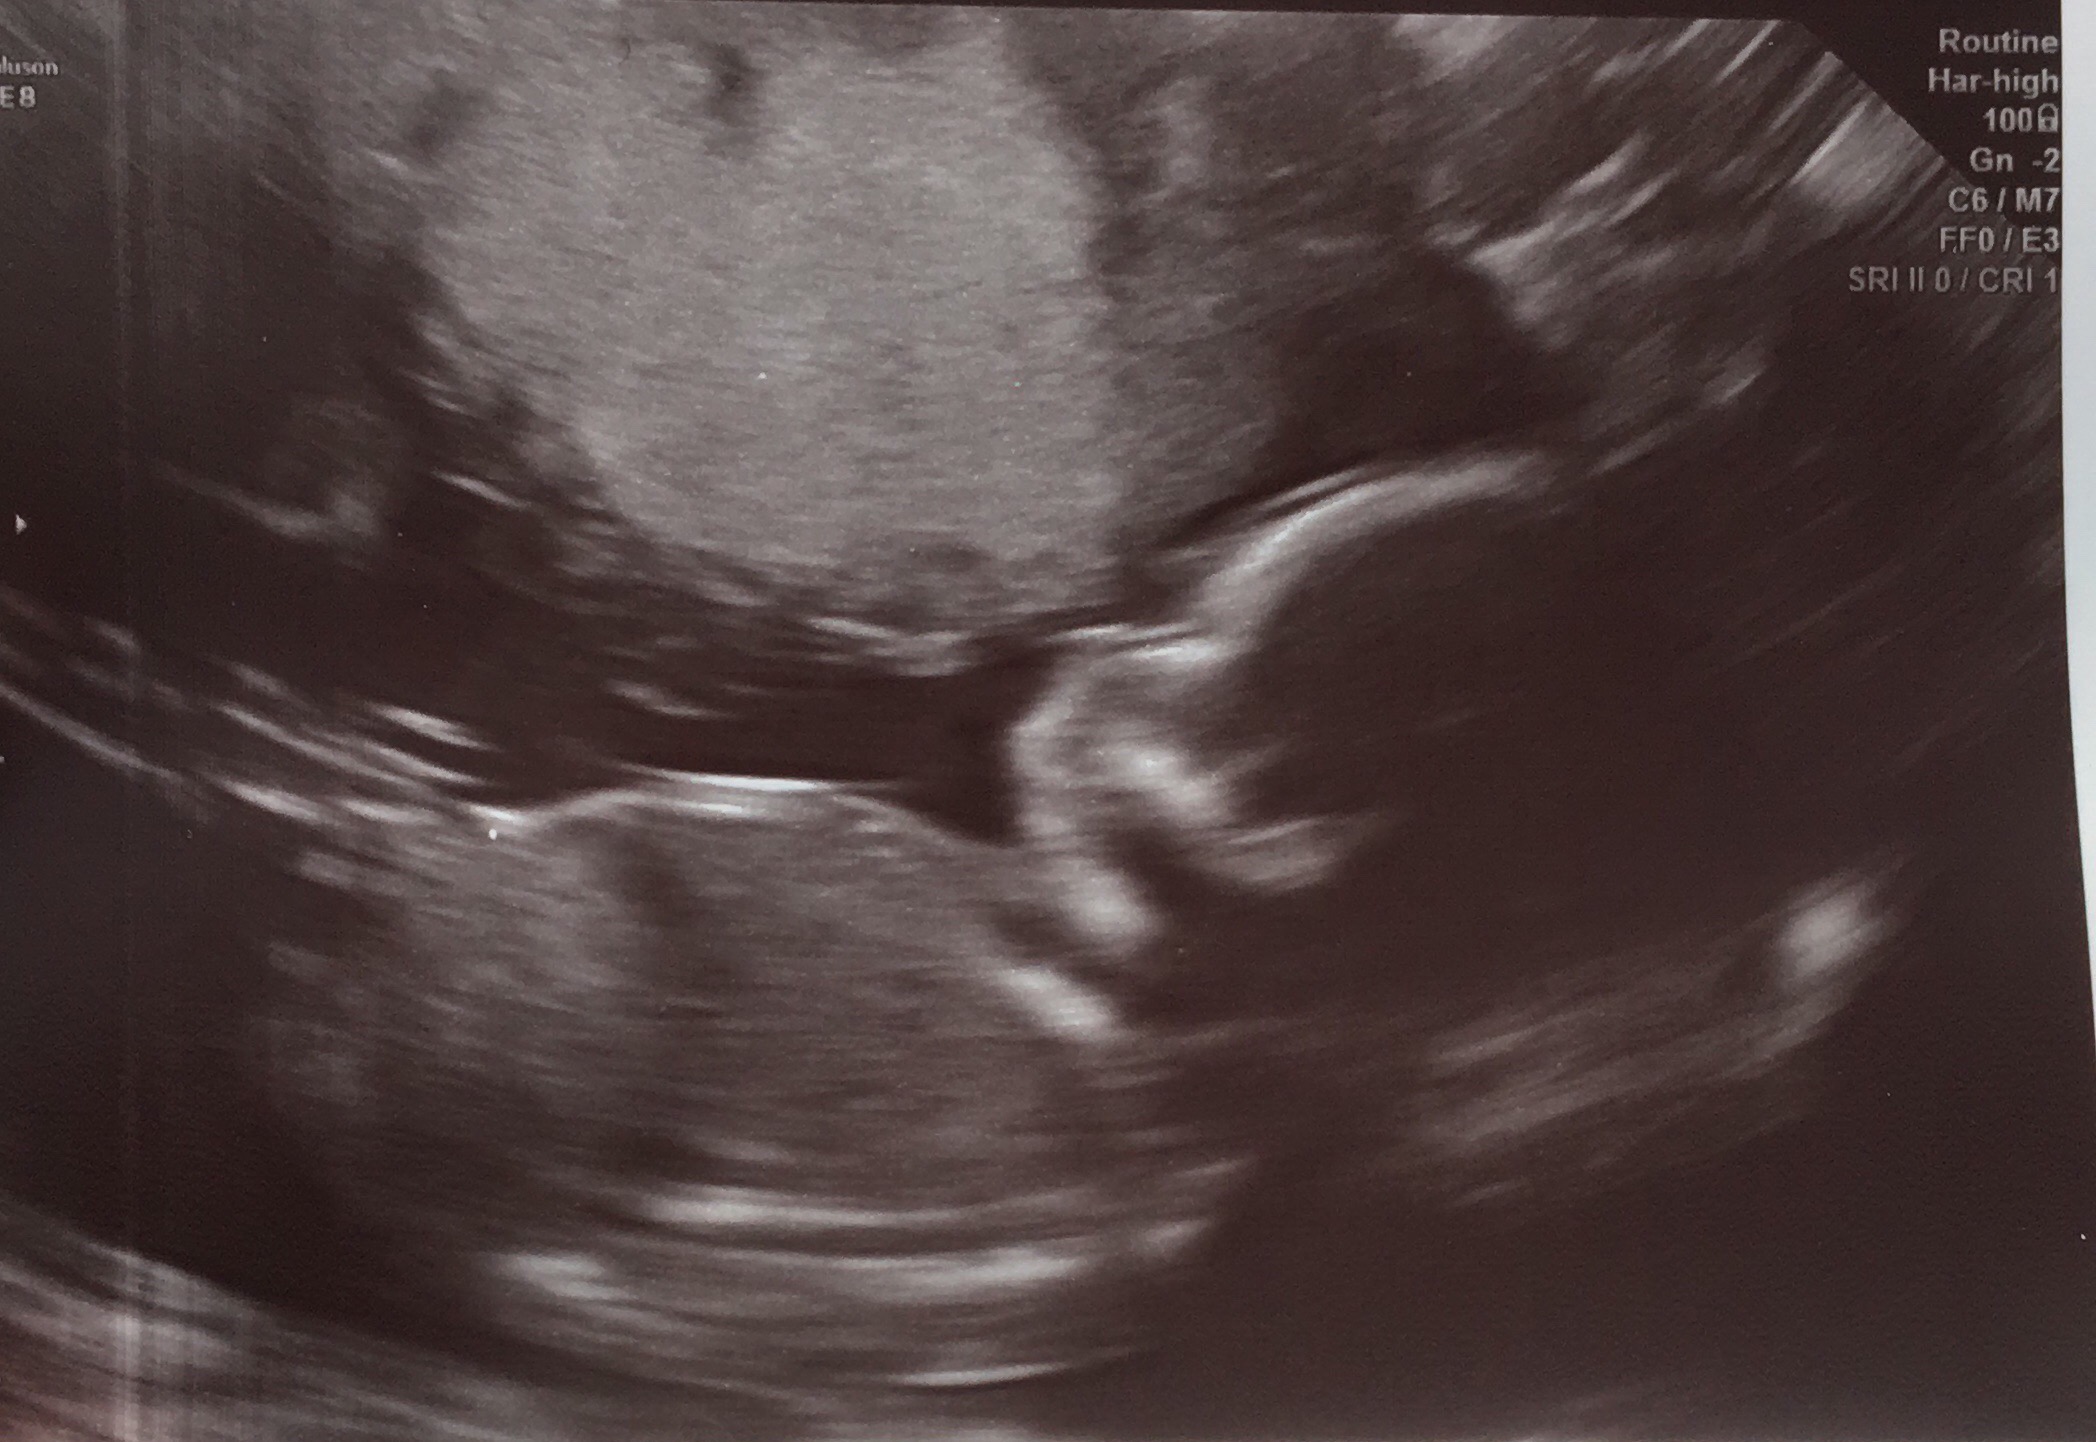

I’ve had both 12 week and 20 week scans and thought I wanted the surprise 3 rd time round but that’s proving more difficult as I approach my 4d scan in Feb. I already have 2 DS and would dearly love a little pink one to complete me but this baby is the last so either way I’m done as financially, spacially and practically we can’t afford anymore.I have thought girl from day one of conception for numerous reasons, timed conception (5-8dpo), feeling very nauseous, strong metallic taste in my mouth which is still present, bad breakouts all of which I didnt have with my boys. I’d be very interested to know what you all think 🤔 Attachment 38554Attachment 38556